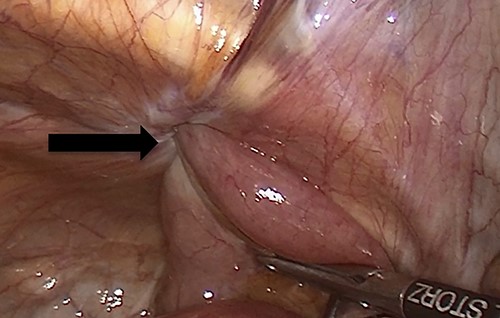

Due to the high-grade small bowel obstruction, the patient was pushed as an emergency case to the operating room. The surgery started and ended as a laparoscopic procedure with three small incisions; 12, 11 and 5 mm port sizes located supraumbilically, right and left midclavicular line relatively. Once the peritoneum was penetrated, and gas insufflated, diagnostic laparoscopy was done, and the obturator hernia with bowel content was visualized (Fig. 3), with a transitional zone at the hernia site showing a proximal dilatation and distal collapse of the small bowel. After that, reduction of the hernia content was subsequently made with no signs of gangrene or ischemia of the bowel. Then, the small bowel was run as a whole to eliminate any other transitional zones or pathology, which was unremarkable. Therefore, as there was no contamination, ischemia or perforation, a Vicryl mesh was elected and inserted as a plug into the obturator opening using a peritoneal flap and fixed (Fig. 4). Once the fixation was obtained, a ProGrip mesh was then applied to cover the whole right area (Fig. 5), which was covered by the peritoneum afterwards. The abdomen was inspected and the bowel looked healthy. Lastly, the ports were removed, the incisions were closed, the skin was clipped and then the dressing was applied.

An intraoperative figure of the obturator hernia transitional zone revealing the hernial sac and protruded bowel segment.